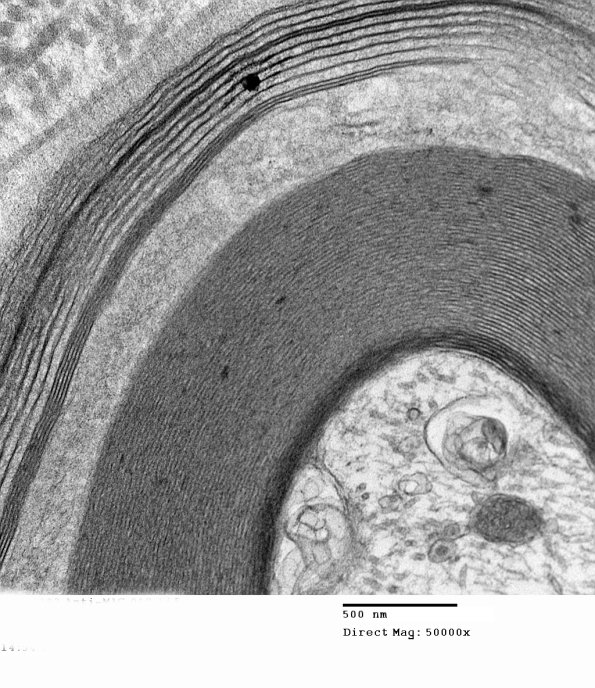

This axon shows wide spaced myelin at several magnifications. The hemi-desmosomes are often seen at nodes but are not typical parts of WSM. (electron micrographs)